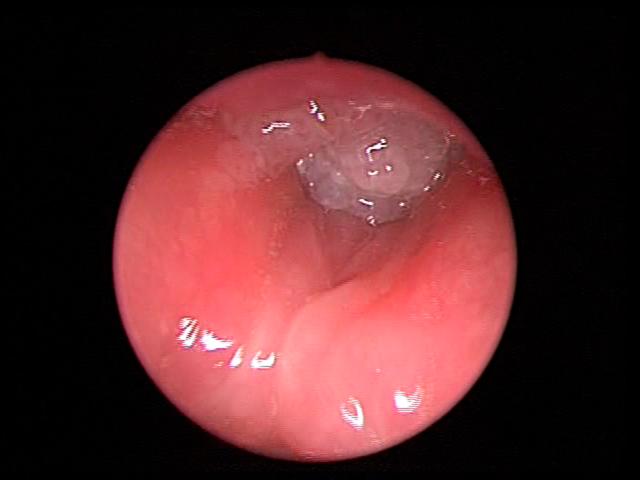

Laryngeal papillomatosis obstructing the glottic inlet.